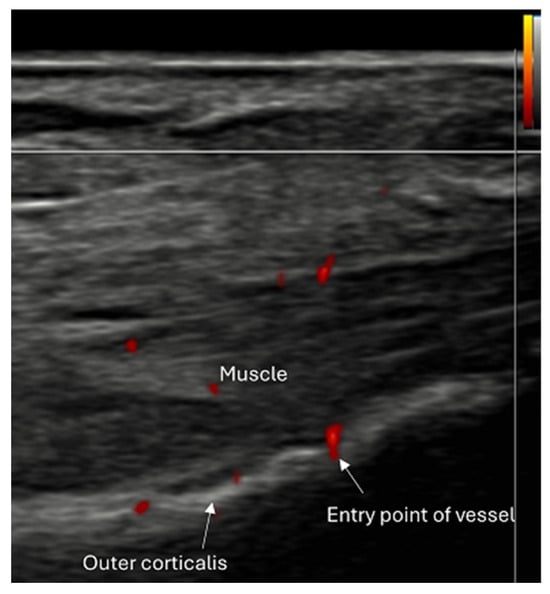

- Use of color and power Doppler: When employing Doppler techniques to assess vascularity related to inflammation or healing, care must be taken to avoid excessive probe pressure. Over compression of the tissue can collapse small vessels, leading to false-negative findings.